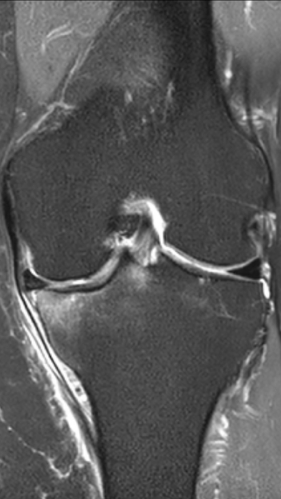

Асептический некроз коленного сустава

4 процедуры ФДТ, 9 процедур MBST, 15 процедур ИПМТ

Параметры изменяются в зависимости от процедуры

Дата публикации: 22.08.2025 14:27:03

3 процедуры ФДТ, 9 процедур MBST, 15 процедур ИПМТ

Дата публикации: 22.08.2025 14:26:54